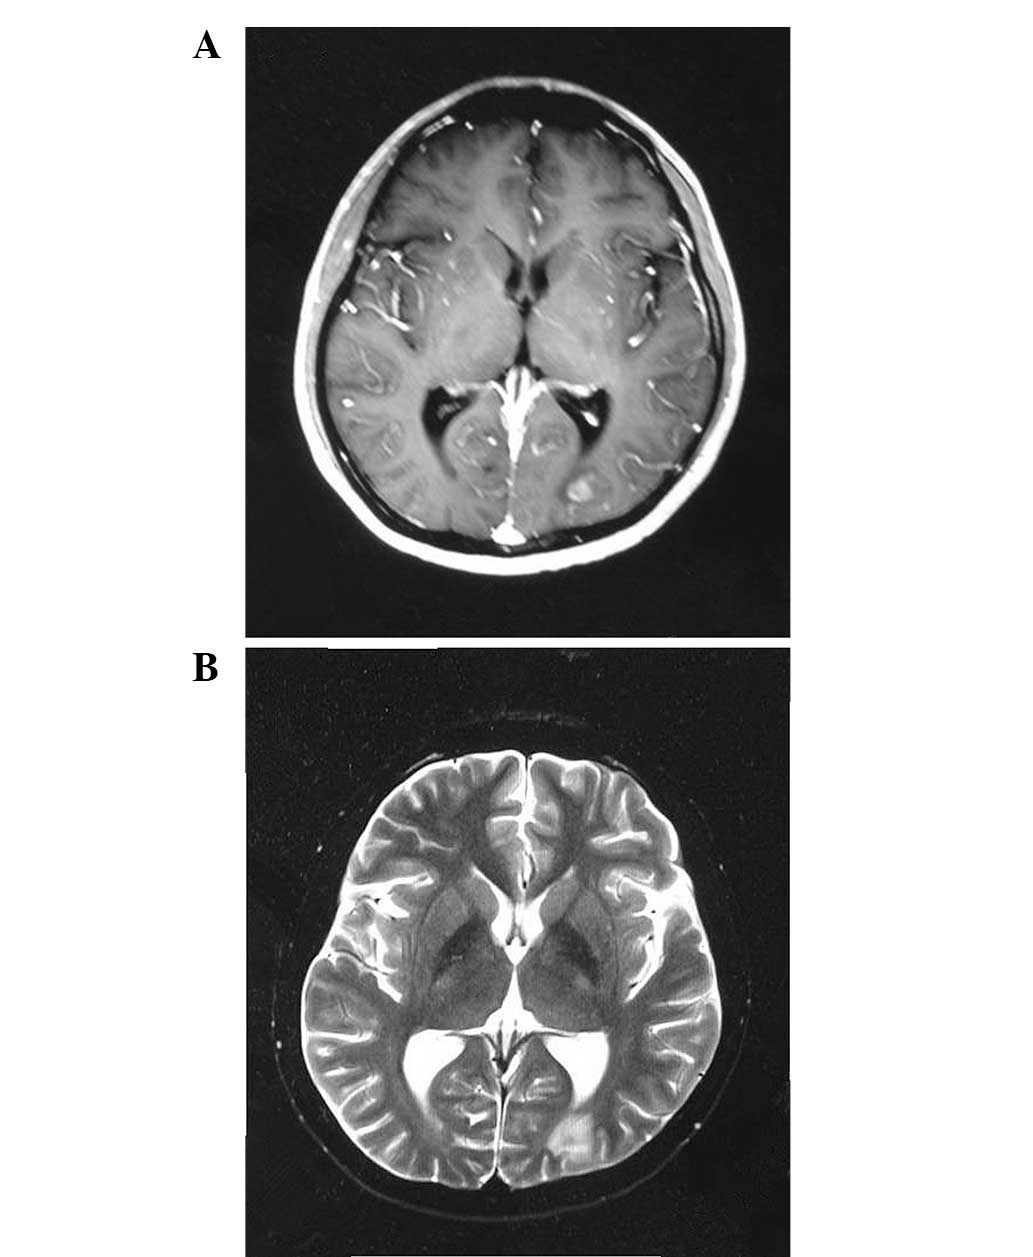

Lymphomatoid granulomatosis involving the central nervous system: A case report and review of the literature

Lymphomatoid granulomatosis (LYG) is a rare tumor with unknown etiology. Specific etiological factors for LYG are also unknown, although previous data indicates that LYG is an Epstein‑Barr virus‑associated B‑cell proliferation associated with an exuberant T‑cell reaction. According to the 2008 WHO classification, LYG is characterized by B‑cell proliferation of B‑lymphoma cells. Generally, treatment options for LYG are similar to those for diffuse large B‑cell lymphoma. Unfortunately, LYG is a chemotherapy‑resistant disease in certain patients and has a poor prognosis. The current study presents the case of a 19‑year‑old male patient with pulmonary LYG. The patient exhibited progressive disease following one cycle of chemotherapy with cyclophosphamide, adriamycin, vincristine and prednisone, and nodular lesions in the brain were diagnosed. Radiotherapy was delivered to the whole brain, however, this treatment did not prevent progression of the disease and the patient succumbed three months after initial presentation. An overview of the literature with regard to the etiology, clinical features, diagnosis and treatment options for LYG is also presented in the current case study.